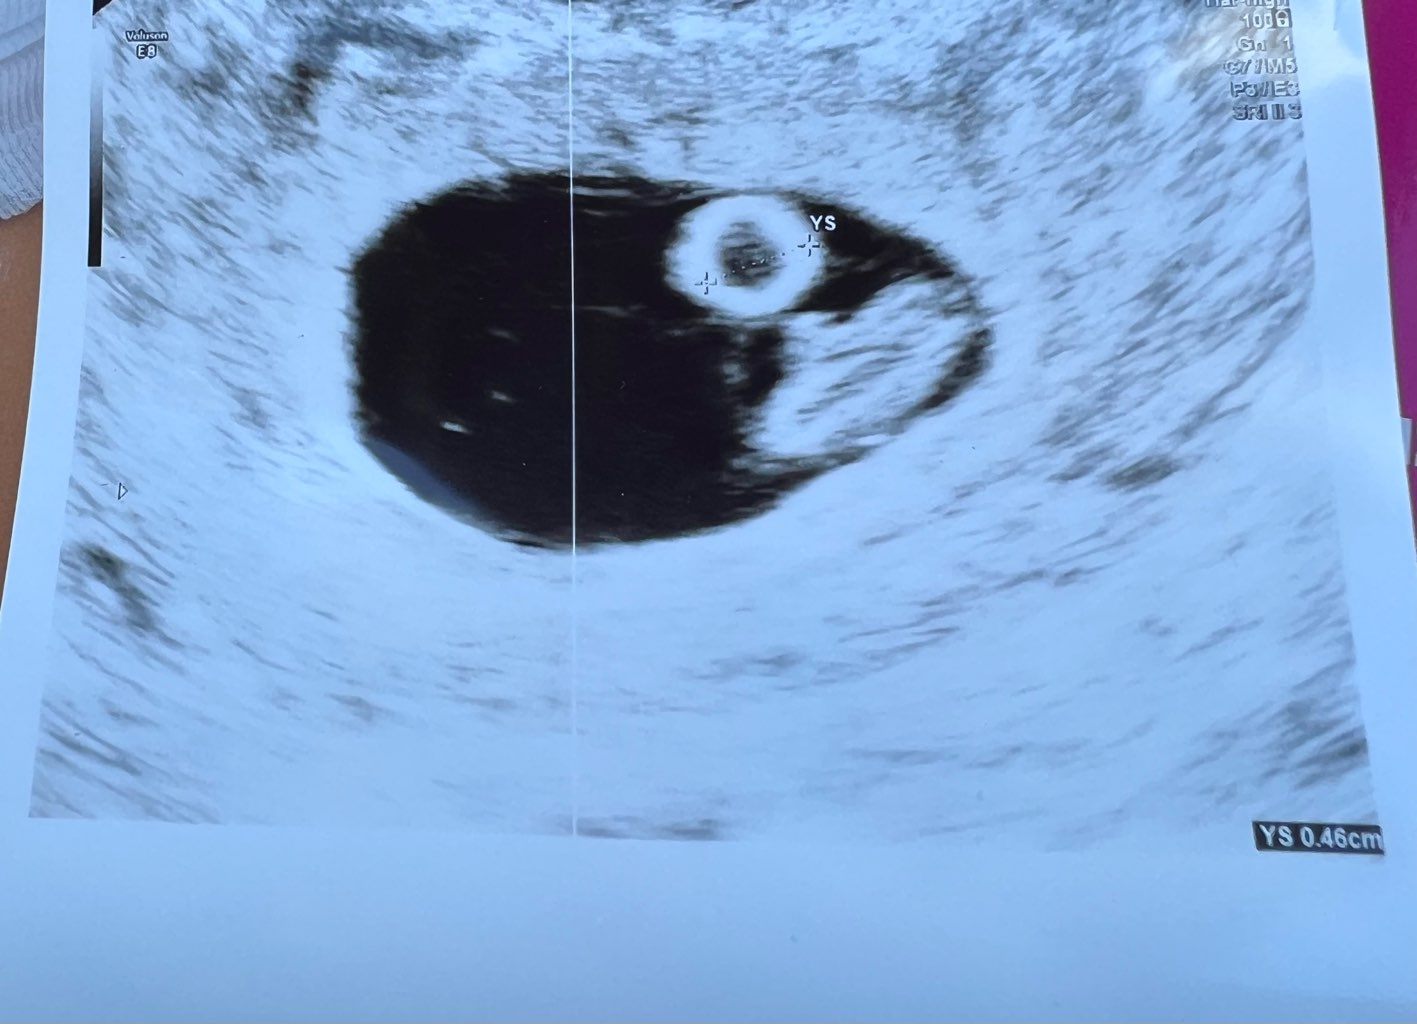

Mamy dorodnego dziecioka z bijącym serduszkiem. Lekarz nie puszczał bo mówił, że dość kontrowersyjna kwestia ostatnio i badania, więc lepiej dmuchać na zimne (choć sam kiedyś puszczał i nie było żadnego wpływu) i dopiero od 10tc lepiej. Wg OM 7+1, a wg USG 7+5 i termin się zmienił z 27.12 na 23.12, ale to jak wiadomo jest ruchome